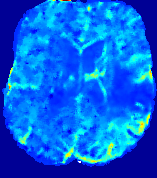

LesionRefer to captionRefer to captionRefer to captionRefer to captionRefer to captionRefer to caption𝐕rgbsubscript𝐕𝑟𝑔𝑏{\bf{V}}_{rgb}Refer to captionRefer to captionRefer to captionRefer to captionRefer to captionRefer to caption𝐕2subscriptnorm𝐕2{\|\bf{V}}\|_{2}Refer to captionRefer to captionRefer to captionRefer to captionRefer to captionRefer to captionRefer to caption3.53.53.52.82.82.82.12.12.11.41.41.40.70.70.70.00.00.0(mm/s)𝑚𝑚𝑠(mm/s)D𝐷DRefer to captionRefer to captionRefer to captionRefer to captionRefer to captionRefer to captionRefer to caption0.0200.0200.0200.0160.0160.0160.0120.0120.0120.0080.0080.0080.0040.0040.0040.0000.0000.000(mm2/s)𝑚superscript𝑚2𝑠(mm^{2}/s)Slice #1Slice #2Slice #3Slice #4Slice #5Slice #6

Figure 3: PIANO feature maps for one stroke patient, where the lesion is located in the left hemisphere. Top row: segmented stroke lesion region (white) on different slices, obtained from ISLES 2017. The corresponding slices for the PIANO feature maps are shown in the following rows.

For a better insight into an estimated velocity field 𝐕𝐕{\bf{V}} and diffusion field 𝐃𝐃{\bf{D}}, we compute the following maps: (1) 𝐕rgbsubscript𝐕𝑟𝑔𝑏{\bf{V}}_{rgb}: Color-coded orientation map of 𝐕=(Vx,Vy,Vz)T𝐕superscriptsuperscript𝑉𝑥superscript𝑉𝑦superscript𝑉𝑧𝑇{\bf{V}}=(V^{x},V^{y},V^{z})^{T}, obtained by normalizing 𝐕𝐕{\bf{V}} to unit length and mapping its 3 components to red, green, blue respectively; (2) 𝐕2subscriptnorm𝐕2\|{\bf{V}}\|_{2}: 222 norm of 𝐕𝐕{\bf{V}}; (3) D𝐷D: scalar field in Eq. 5.

Fig. 3 and Fig. 4 show the PIANO feature maps estimated from two ISLES 2017 patients: all are highly consistent with the lesion in both cases. Details of the blood flow trajectories are revealed in 𝐕rgbsubscript𝐕𝑟𝑔𝑏{\bf{V}}_{rgb} by the ridged patterns and the sharp changes of colors in the unaffected (right) hemisphere, while the flat patterns appearing within the lesion provide little directional information about the velocity and indicate low velocity magnitudes. Velocity magnitudes are more directly visualized via 𝐕2subscriptnorm𝐕2\|{\bf{V}}\|_{2}, from which one can easily locate the lesion where 𝐕2subscriptnorm𝐕2\|{\bf{V}}\|_{2} is low. D𝐷D also indicates lower diffusion values in the lesion, though with less contrast potentially due to the fact that it captures the accumulated effect of CA diffusion at the voxel-level.